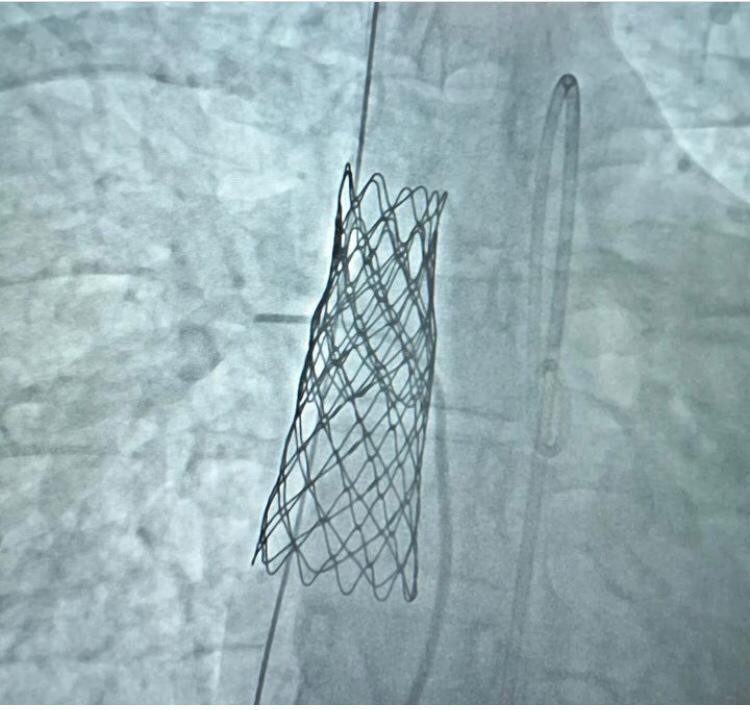

Kardiyoloji Kliniği Sorumlusu Prof. Dr. Mehmet Ali Astarcıoğlu, “Kütahya’da ilk başarılı sinüs venosus tipi atriyal septal defekt kapatma işlemi yapıldı. Ekip olarak, 23 yaşındaki genç hasta Aslı Şahin’e başarılı bir işlem gerçekleştirerek hastanemizde ilkleri yaşamaya devam ediyoruz. ’ASD lokalizasyonuna göre sekundum, primum, sinüs venosus ve koroner sinüs tip olmak üzere dört farklı şekilde görülebilir. Bunlardan sekundum tip ASD dışında diğerlerinin tedavisi açık kalp cerrahisidir. Sinüs venosus tipi ASD, tüm ASD lerin yüzde 5-10’unu oluşturur. Sağ kalbe gelen büyük toplardamarlar ile sol kulakçığı ayıran atriyum dokusunun gelişim bozukluğu sonucu oluşur. Sinüs venosus atriyal septal defektlerin görüntülenmesi ve tedavisinde son birkaç yılda önemli bir paradigma değişikliği oldu. Bu gelişmelerin sonucu olarak kapalı stentler artık bu defektlerin perkütan (Ameliyatsız) olarak kapatılmasına imkan sağladı” diye konuştu.